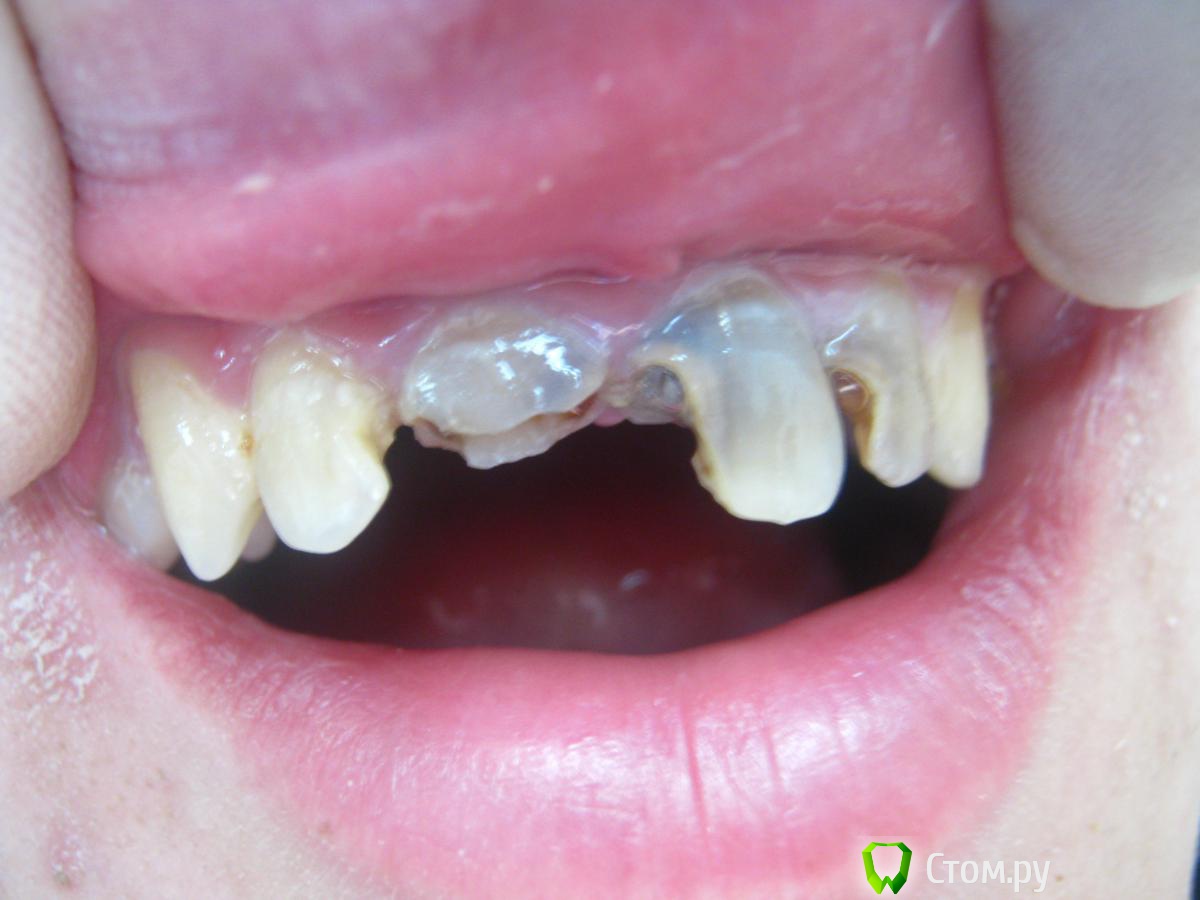

Abdul9848 Опубликовано 24 ноября, 2013 Поделиться Опубликовано 24 ноября, 2013 Выставляю на суд, фото препарированных культей скину позже.на зубах 11 21 культевые вкладки. 1 Ссылка на комментарий

Heatshock Опубликовано 25 ноября, 2013 Поделиться Опубликовано 25 ноября, 2013 (изменено) для первого раза не плохой результат. Но нету фото с улыбкой,т.е. сложно определить попали ли Вы в эстетику.Мне лично куда интереснее чего там под коронками и чего с ферулом. пс: важно чтобы пациент был доволен, но ставить этот момент, как самый важный не правильно. Вот конкретно в данный момент он может и доволен, а через год может уже и не будет. Многие врачи идут на поводу у пациентов и лечат те зубы которые просит сам пациент. Довон ли пациент? Конечно. А правильно ли это? Безусловно нет. Изменено 25 ноября, 2013 пользователем Heatshock Ссылка на комментарий

Abdul9848 Опубликовано 25 ноября, 2013 Автор Поделиться Опубликовано 25 ноября, 2013 для первого раза не плохой результат. Но нету фото с улыбкой,т.е. сложно определить попали ли Вы в эстетику.Мне лично куда интереснее чего там под коронками и чего с ферулом. пс: важно чтобы пациент был доволен, но ставить этот момент, как самый важный не правильно. Вот конкретно в данный момент он может и доволен, а через год может уже и не будет. Многие врачи идут на поводу у пациентов и лечат те зубы которые просит сам пациент. Довон ли пациент? Конечно. А правильно ли это? Безусловно нет.там феррула нет совсем. по причине отсутствия феррула не сделал одиночные 1 Ссылка на комментарий

Heatshock Опубликовано 25 ноября, 2013 Поделиться Опубликовано 25 ноября, 2013 там феррула нет совсем. по причине отсутствия феррула не сделал одиночныет.е. чтобы сразу обе коронки выпали, а не по отдельности? а почему не сделали удлинение корня? Ссылка на комментарий

Abdul9848 Опубликовано 25 ноября, 2013 Автор Поделиться Опубликовано 25 ноября, 2013 т.е. чтобы сразу обе коронки выпали, а не по отдельности?а почему не сделали удлинение корня?нет, чтоб нагрузка распределилась на 4 зуба, удлинение корня вы имеете ввиду хирургически ? 1 Ссылка на комментарий

Abdul9848 Опубликовано 25 ноября, 2013 Автор Поделиться Опубликовано 25 ноября, 2013 даКонечно можно было сделать, если бы тут где я прохожу интернатуру были условия и делал бы кто ни будь такие операции, плюс к этому, пациент финансово не тянул больше расходов, одним словом ограничения со всех сторон. к тому же я интерн. 1 Ссылка на комментарий

4ebstom Опубликовано 25 ноября, 2013 Поделиться Опубликовано 25 ноября, 2013 На будущее-старайтесь подходить к лечению комплексно,восстанавливая и боковые сегменты. Ссылка на комментарий